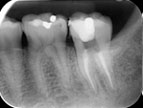

Đưa file vào ống tủy để xác định chiều dài chân răng.